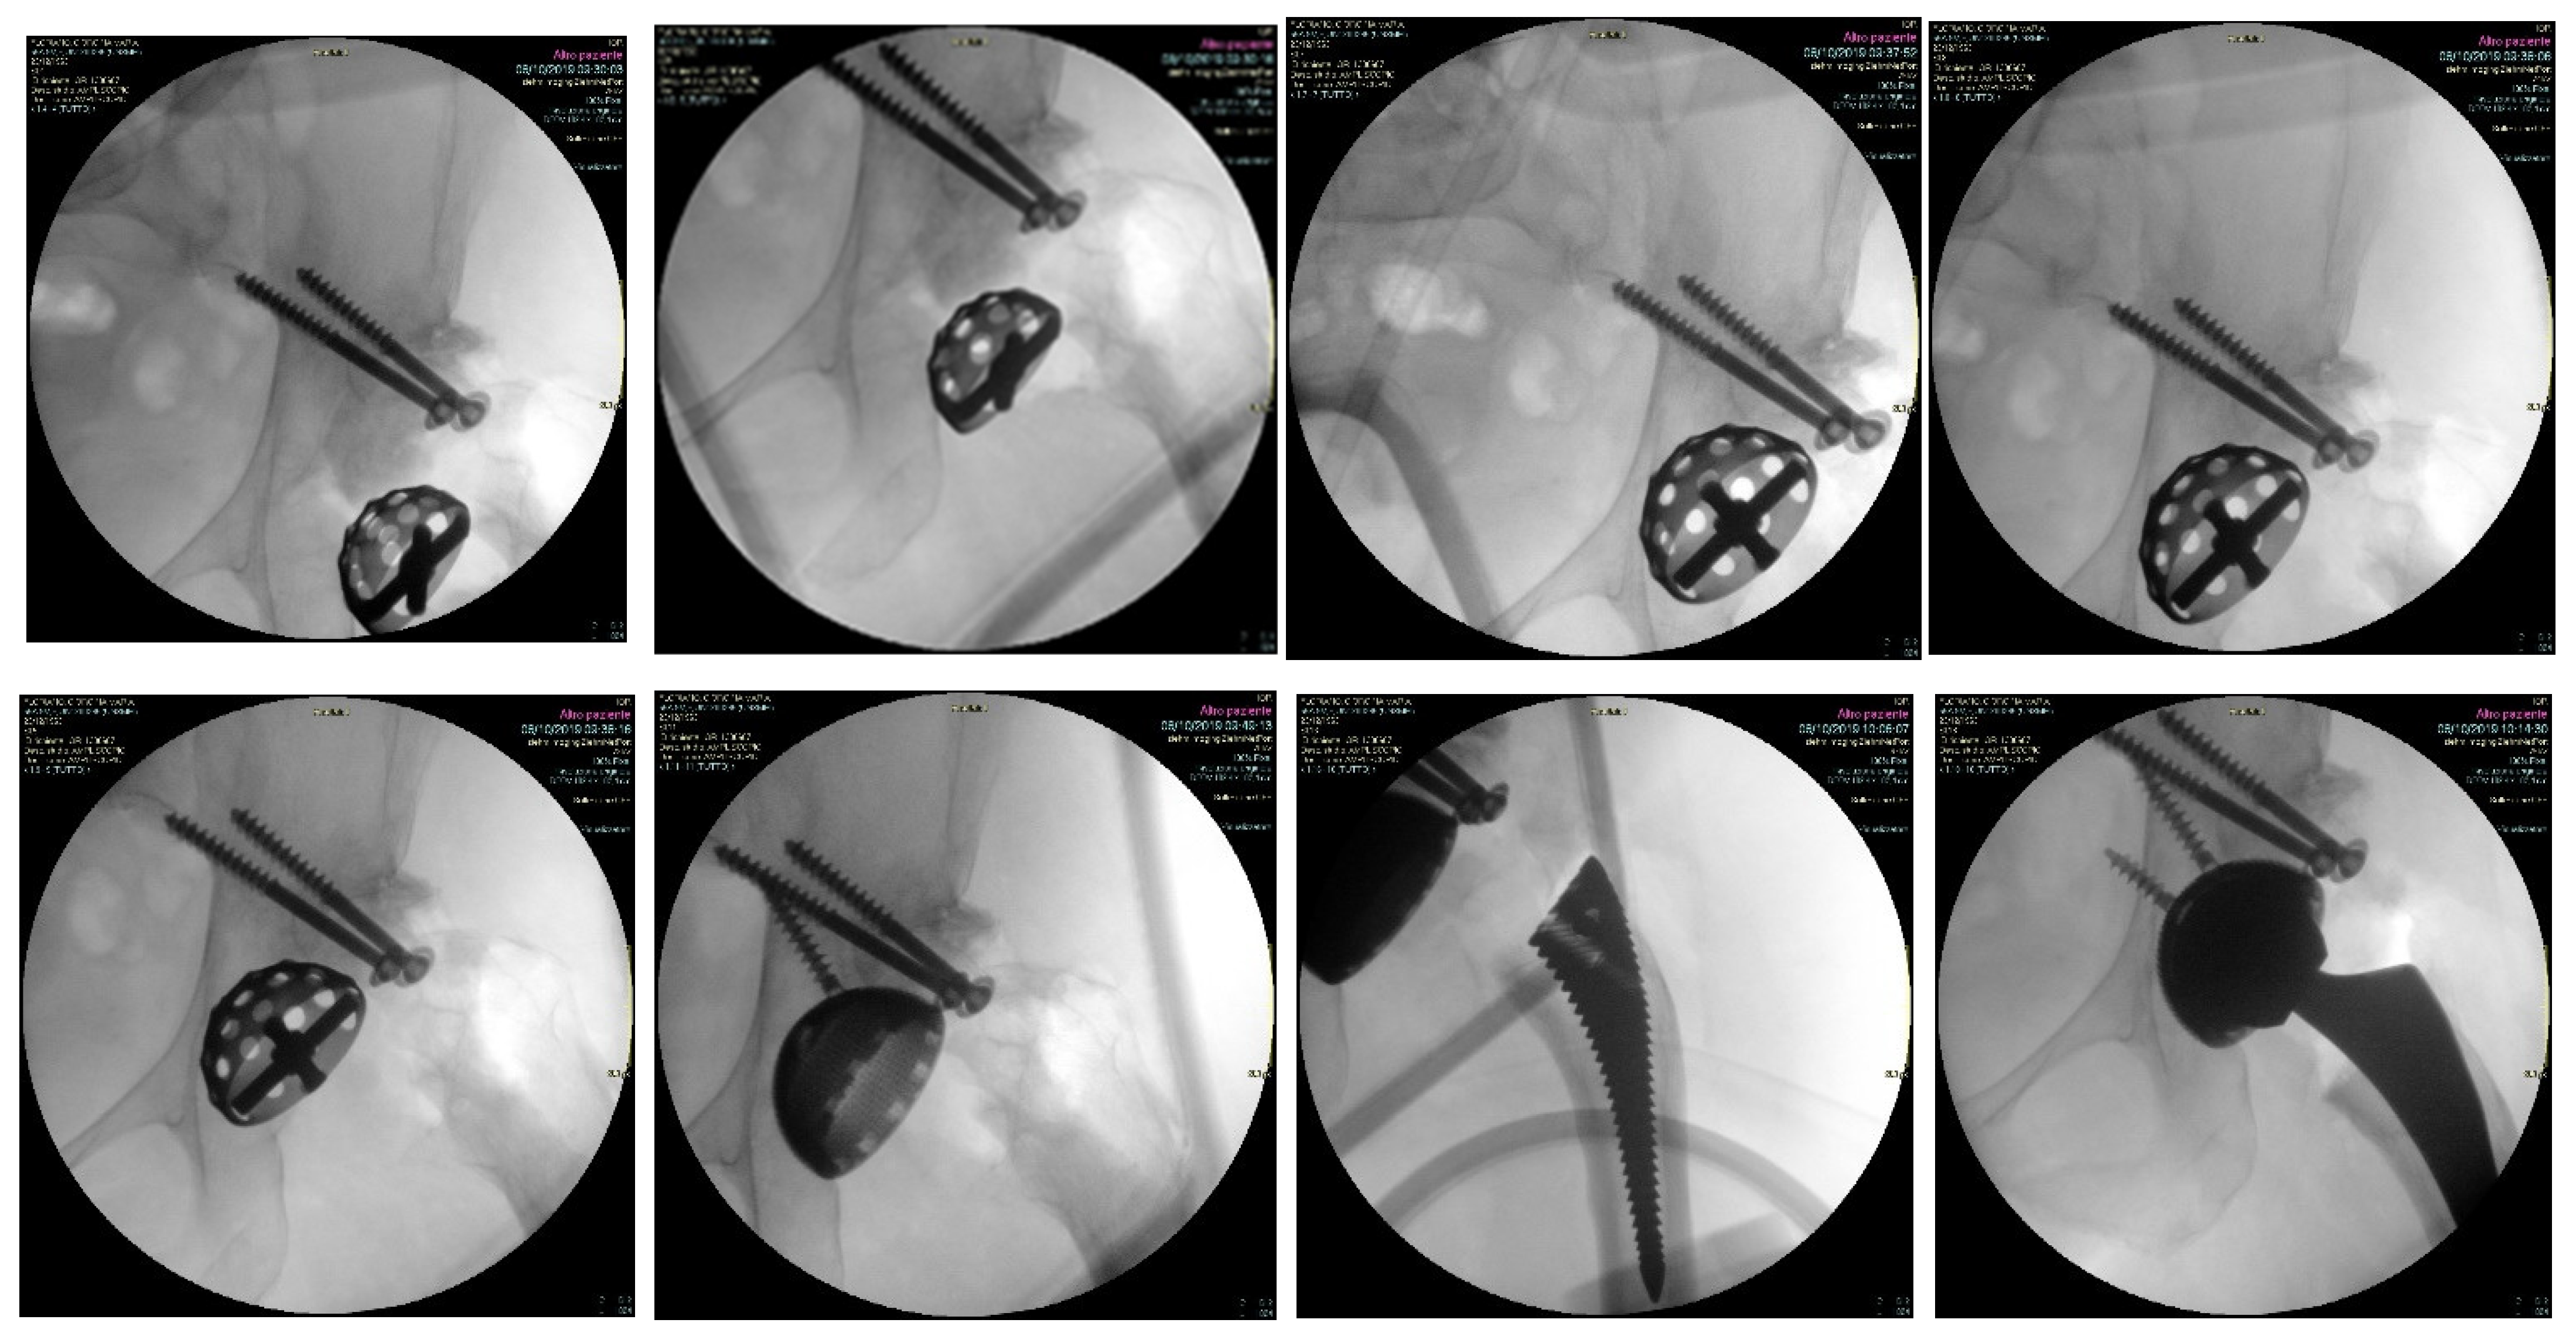

2.1. Surgical Technique